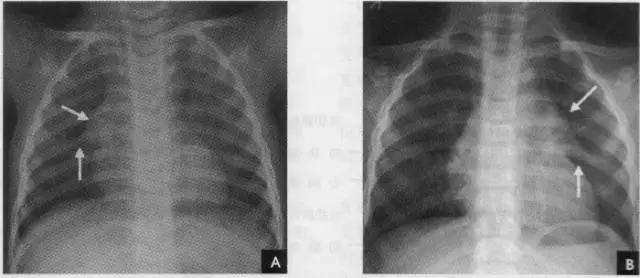

(七)肺纹理 肺纹理为自肺门向肺野呈放射状分布的树枝状阴影,它主要是肺动脉的投影,肺静脉、支气管和淋巴管也参与形成。平片可显示肺纹理的多少,粗细.分布,有无扭曲、变形与移位等。肺纹理由肺门向外围延伸,逐渐变细,至肺野外带渐细小而稀少,距侧胸壁内缘约1cm范围内的肺野基本无肺纹理可见(图下图)。